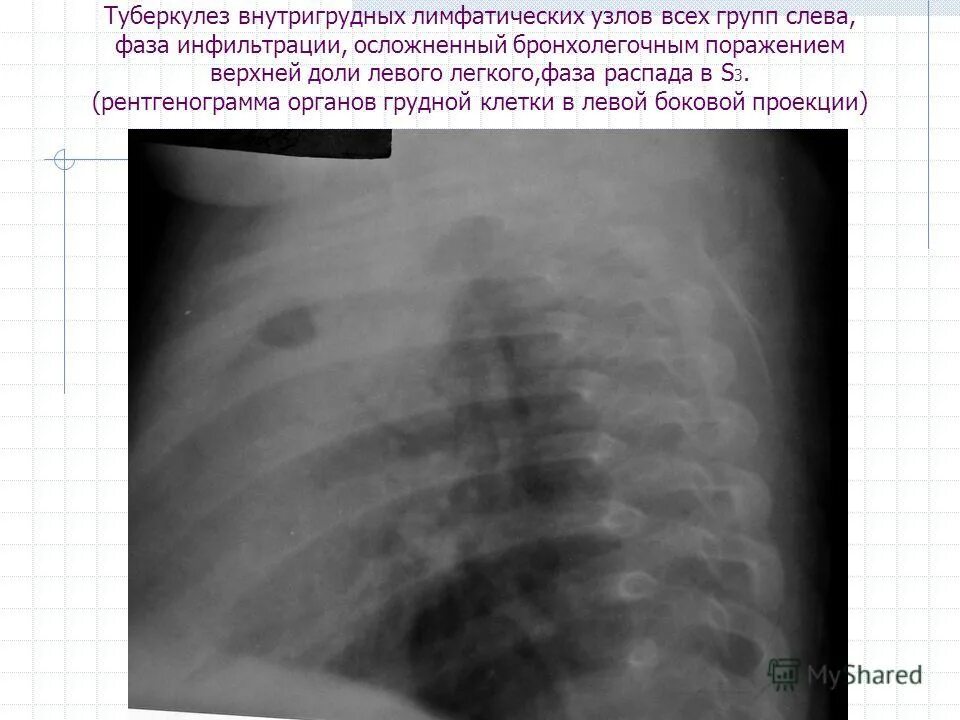

S1 2 слева